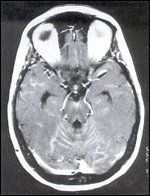

FIGURE 2

MRI of Leptomeningeal Metastases

Her ventricular CSF contained normal protein and glucose concentrations but was never free of malignant cells. She did well clinically, however, continuing to work and travel. Her neurologic examination was normal aside from distal sensory loss in the lower extremities consistent with a mild peripheral neuropathy. However, in September 1999, she developed persistent diarrhea, nausea, and vomiting and was found to have an obstructed bile duct caused by peritoneal seeding of her carcinoma. Her brain MRI now demonstrated diffuse and nodular leptomeningeal contrast enhancement (Figure 2). She was lost to follow-up and presumably died shortly thereafter.